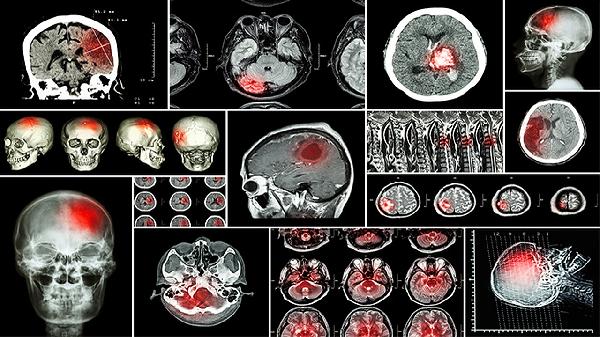

脑癌晚期症状有哪些

脑癌晚期症状主要包括剧烈头痛、视力障碍和肢体无力,需及时就医进行针对性治疗。头痛常伴随恶心呕吐,视力模糊或视野缺损可能与肿瘤压迫视神经有关,肢体无力则因肿瘤影响运动中枢。治疗手段包括手术切除、放疗和化疗,同时需配合营养支持和心理疏导。

1、剧烈头痛:脑癌晚期患者常出现持续性或间歇性剧烈头痛,尤其是早晨起床时更为明显。这种头痛通常由颅内压增高引起,可能伴随恶心、呕吐等症状。治疗上,医生会根据患者情况使用降颅压药物如甘露醇,同时结合止痛药物缓解症状。

2、视力障碍:肿瘤压迫视神经或视觉中枢可能导致视力模糊、视野缺损甚至失明。患者可能出现看东西重影、视力下降等症状。治疗方案包括手术切除肿瘤以减轻压迫,或通过放疗缩小肿瘤体积,改善视力。

3、肢体无力:脑癌晚期患者可能出现单侧或双侧肢体无力、麻木,严重时甚至瘫痪。这与肿瘤侵犯运动中枢或传导通路有关。康复治疗包括物理疗法、运动训练,必要时可使用神经营养药物促进神经功能恢复。

4、认知功能障碍:晚期脑癌患者可能出现记忆力减退、注意力不集中、语言障碍等认知功能下降表现。这与肿瘤侵犯相关脑区或颅内压增高有关。治疗上,除针对肿瘤本身的治疗外,可进行认知功能训练,必要时使用改善脑代谢的药物。

5、癫痫发作:部分脑癌晚期患者可能出现癫痫发作,表现为肢体抽搐、意识丧失等。这与肿瘤刺激脑组织或影响神经传导有关。治疗包括抗癫痫药物如丙戊酸钠、卡马西平等,必要时可考虑手术切除致痫灶。

6、内分泌紊乱:当肿瘤位于垂体或下丘脑附近时,可能导致内分泌功能紊乱,如性欲减退、月经不调、体重异常等。治疗上需针对具体激素水平异常进行替代治疗,同时积极控制肿瘤生长。

7、精神症状:部分患者可能出现情绪波动、性格改变、幻觉等精神症状。这与肿瘤位置及对脑功能的影响有关。治疗包括心理疏导、抗精神病药物使用,同时积极控制原发病。

脑癌晚期症状复杂多样,需根据具体表现采取针对性治疗。除积极治疗肿瘤本身外,还需关注患者的生活质量,提供全面支持。及时就医、规范治疗是改善预后的关键,同时患者及家属应积极配合制定个性化治疗方案,并注意日常护理和心理支持。